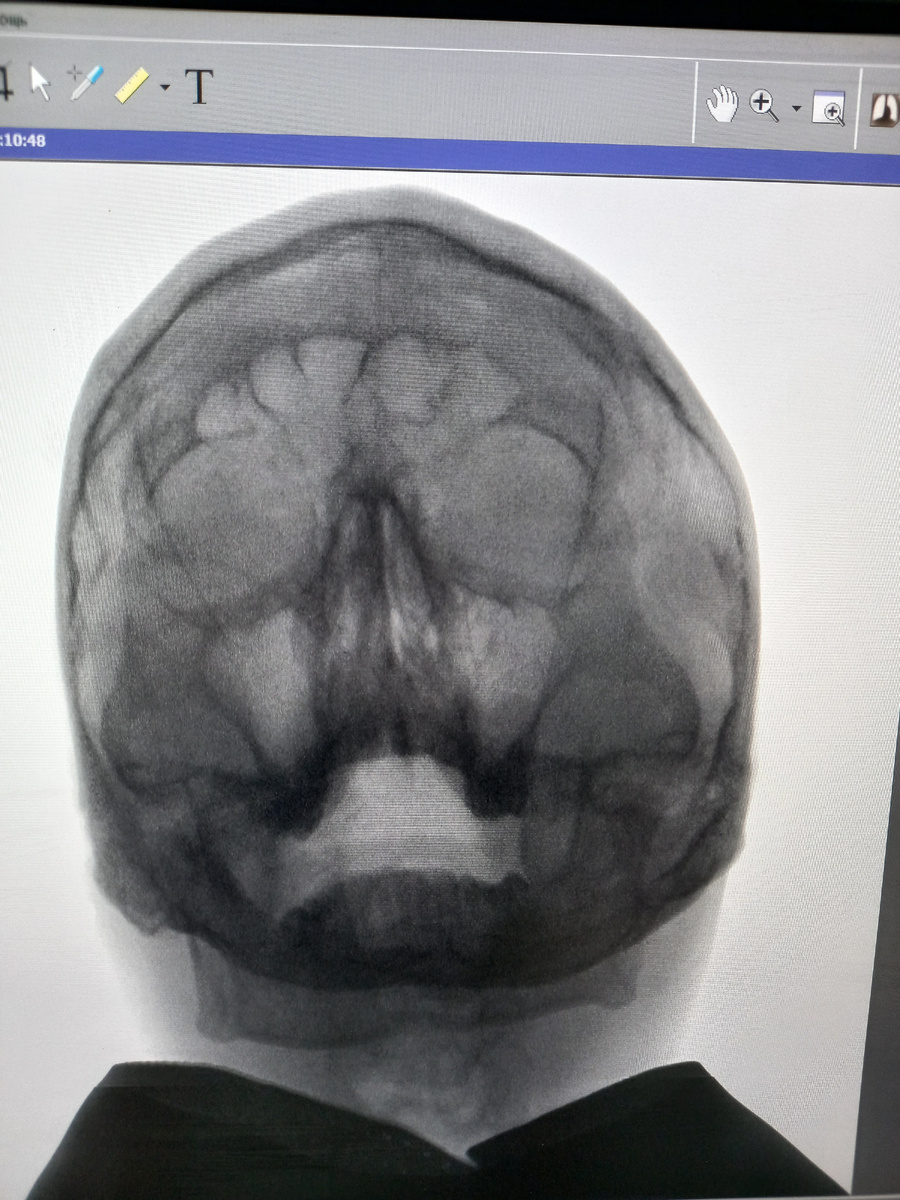

Рентген снимок головы